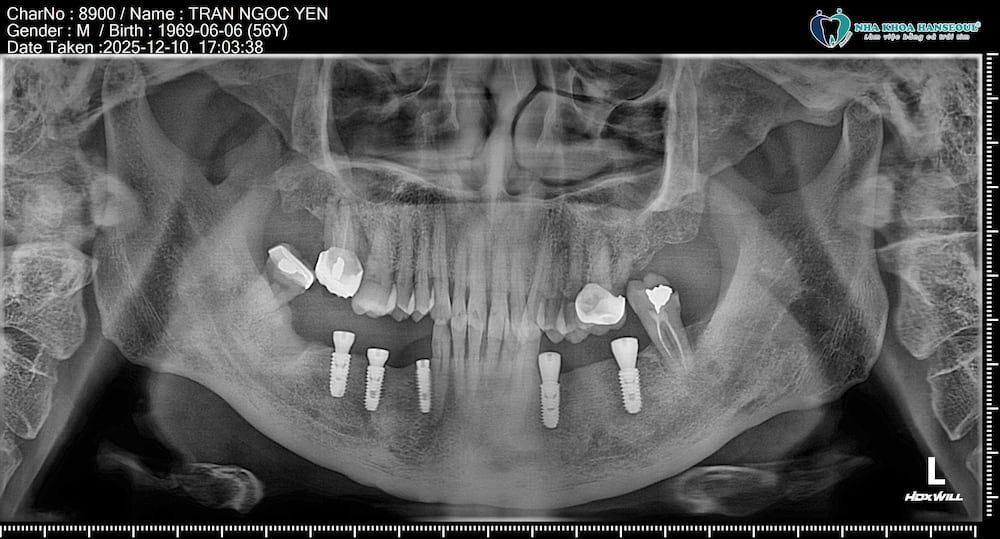

Kết quả sau điều trị

Ngay sau khi hoàn thành cấy ghép:

5 trụ implant được đặt chắc chắn, đúng vị trí theo kế hoạch.

Mô mềm quanh implant ổn định, ít sưng, chú ăn uống nhẹ bình thường trong ngày.

Cảm giác đau gần như không đáng kể, chú chỉ dùng thuốc theo hướng dẫn và sinh hoạt bình thường.